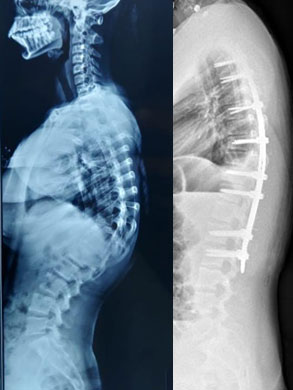

Some of the spinal corrections: